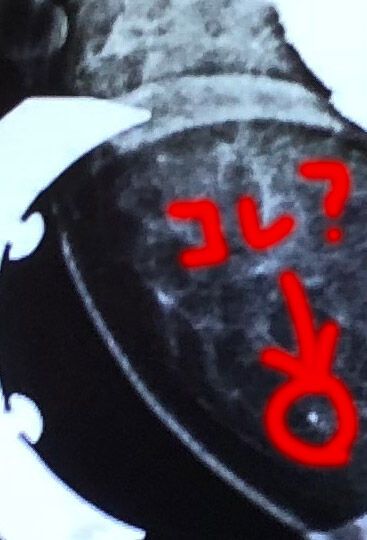

朝受けたマンモグラフィの結果は、要精密検査。

多分、この丸をした範囲に石灰化が見られるというものでした